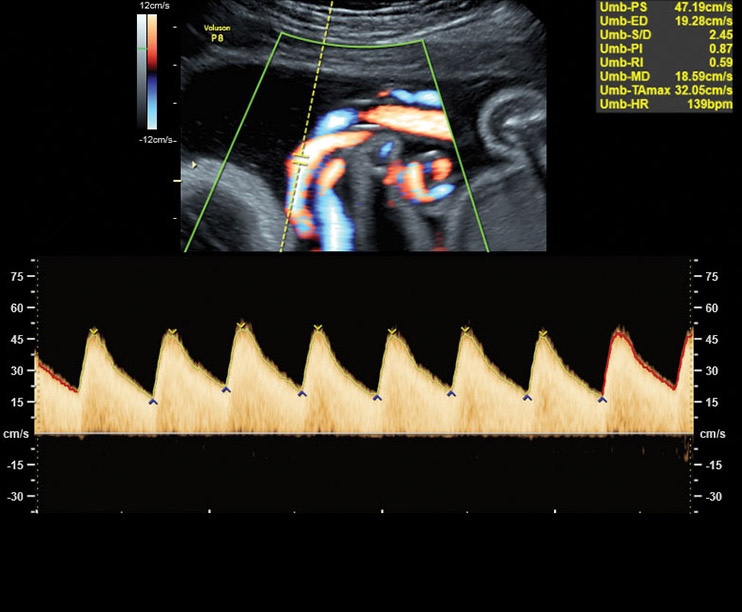

Высокочастотный импульсный допплер:

Да

Цветовой допплер:

• Работа в В-, М-режимах, наличие импульсно-волнового, цветного допплеровского картирования, тканевого, энергетического и высокочувствительного направленного энергетического допплера (HD-Flow), тканевая гармоника

• Высокочувствительный допплер (HD-Flow), многолучевое сложносоставное сканирование (CRI), Speckle Reduction Imaging (SRI), SonoBiometry (автоматическое измерение BPD, AC, HC, HL, FL)